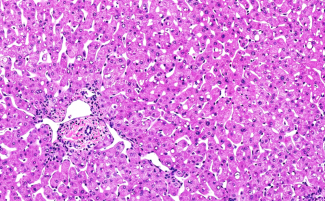

Primary human hepatocytes, Kupffer cells, stellate cells and liver endothelial cells, and accompanying media and media recommendations round out our research offerings to recapitulate the human liver in vitro. Additional tools comprise access to donated human livers – whether as the whole gift itself or as snap-frozen tissue or formalin fixed paraffin embedded tissue. Other tissues and cells are also available upon request.